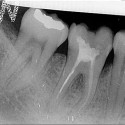

Foto 1: Situazione iniziale: radiografia del molare inferiore destro fratturato (il 46)

Foto 2: Radiografia dell’impianto al molare inferiore destro (il 46)

Foto 6: Risultato finale: la corona in porcellanaLa paziente presentava il molare inferiore destro (il 46) da estrarre per frattura della corona e della radice.

In anestesia locale, si procede alla rimozione del molare fratturato e, contestualmente, all’inserimento di un impianto dentale immediato che sostituisce la radice estratta.Viene anche effettuato un piccolo innesto di osso per migliorare il sostegno dei tessuti molli (gengiva) periimplantari.

L’innesto è coperto da membrana in doppio strato per proteggerlo dal riassorbimento fisiologico.

La gengiva viene suturata e l’impianto risulta transmucoso (cioè, si vede la testa del pilastro di guarigione a filo della gengiva).La guarigione del tessuto osseo perimplantare richiede tre mesi perché occorre dare tempo all’organismo di formare nuovo osso, dove sono state estratte le radici del molare; infatti l’impianto non ha la stessa forma delle radici rimosse.

Decorso tale periodo si rileva un’impronta e si confeziona la corona in porcellana.